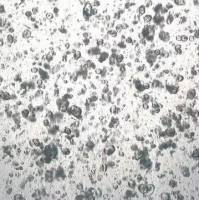

CRL-2557 Panc 05.04 人胰腺癌细胞